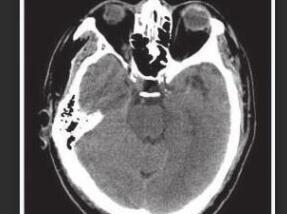

1小时条评论患者女性,72岁,主因发作性双眼向右侧凝视12天,左侧肢体抽动1周于2005年12月30日收入院。患者入院前12天无明显诱因反复出现发作性双眼向右侧凝视、头向右侧扭转,每天发作数次,每次持续不到30秒,未到医院就诊。5天后发作时伴左侧肢体抽动,左上肢屈曲,左下肢强...